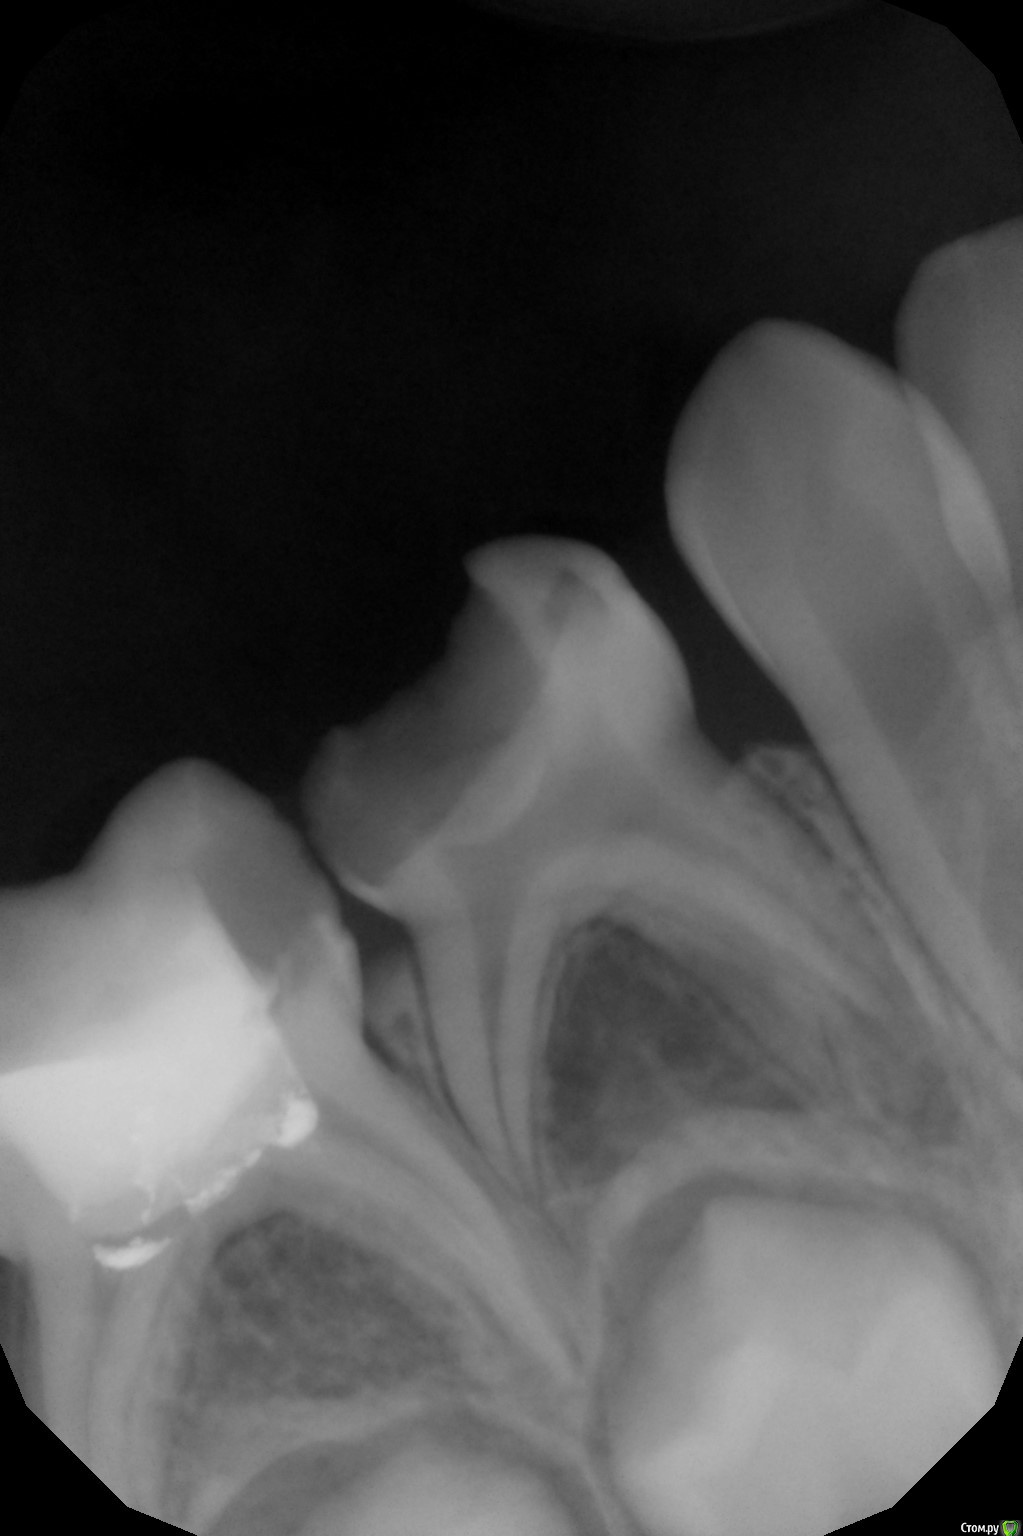

crown Опубликовано 5 апреля, 2016 Поделиться Опубликовано 5 апреля, 2016 Ничего особенного, стандартная ситуация. Зуб 8.4, ребенку 5,5 лет. В бифуркации не четкий рисунок. Зуб не беспокоит, зондирование болезненно. Витальная ампутация? или все таки лезть в каналы? Ссылка на комментарий

CRAZYDUCK Опубликовано 5 апреля, 2016 Поделиться Опубликовано 5 апреля, 2016 (изменено) А я бы после ампутации посмотрела -если гемостаз хороший ,то ампутация, ну если кровит , то витальная экстирпация в одно посещение .На снимке часто бывает нечеткий рисунок в зоне бифуркации, а в зубе -все "спокойно" Изменено 5 апреля, 2016 пользователем CRAZYDUCK Ссылка на комментарий